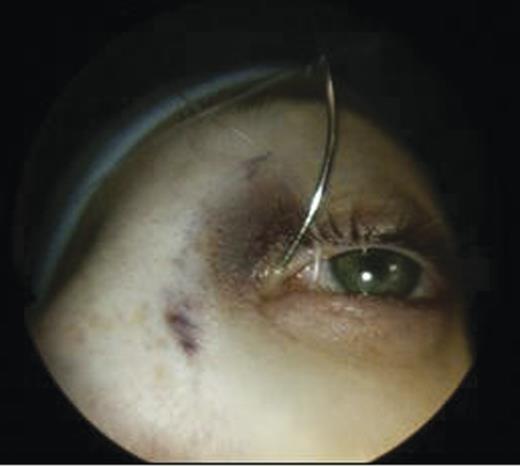

Clinical examination revealed a small cystic swelling in her left medial canthus (Fig. 1). There was no discharge on pressure, mild tenderness was elicited and the swelling was not compressible. The rest of the eye examination was normal with a visual acuity of 6/6 in both eyes.